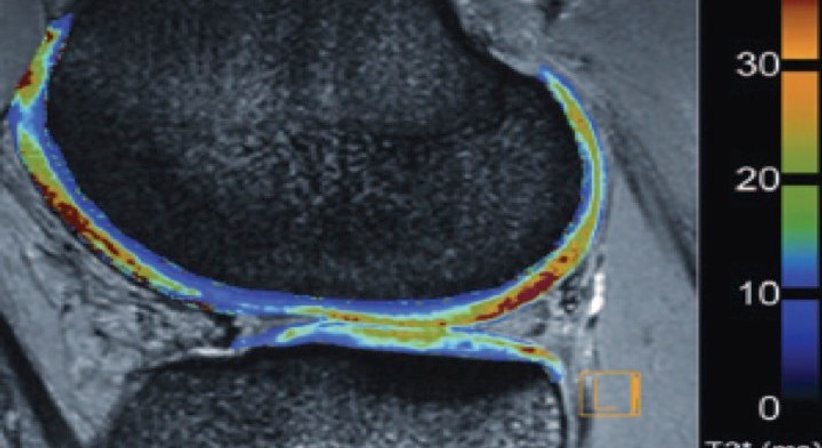

· Knorpelschaden

Knorpelschäden werden meist durch degenerative Veränderungen am Kniegelenk verursacht. Zudem können chronische Instabilitäten und entzündliche Erkrankungen eine Schädigung der Knorpel beschleunigen. Die Behandlung erfolgt in den meisten Fällen arthroskopisch.